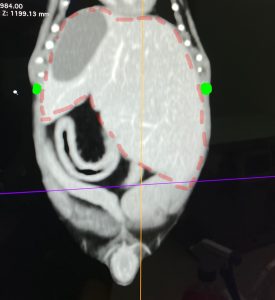

CT画像

肝臓は赤い点線内です。緑点は最後肋骨になります。